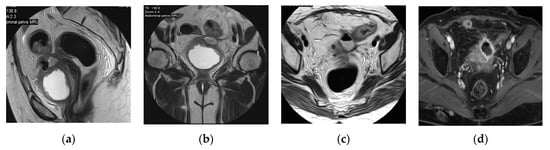

2.12. Cystitis

2.13. Eosinophilic Cystitis

2.14. Cystitis and Fistula

2.15. Acute Bacterial Prostatitis and Prostatic Abscess

| Acute infectious cystitis | Diffuse bladder wall thickening, especially if oedematous at T2 weighted image, urothelial hyperenhancement, perivesical fat stranding. |

| Mural bladder abscess | Intramural/exophytic non-enhancing fluid collection, irregular wall, often thick peripheral enhancement, usually affecting the upper bladder aspect. |